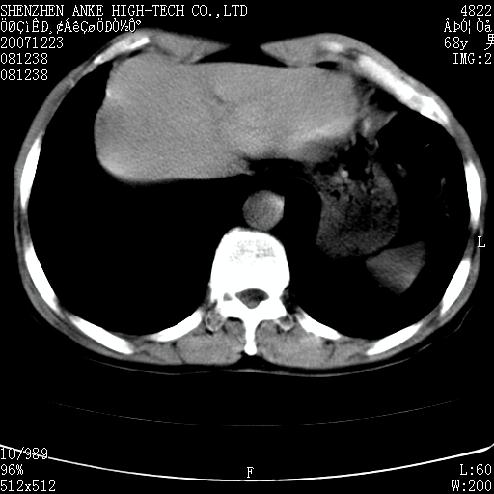

患者:男,63岁,2年前胆囊切除术后,现右上腹部剧烈疼痛近2天.

请看第一张正位片,胸主动脉象有扩张,胸主动脉瘤?

未见异常,病人差闭气,伪影较多.

肠道准备不好,干扰影大。

肠道气体伪影干扰太大了,应该是干扰所致,未见明显异常。